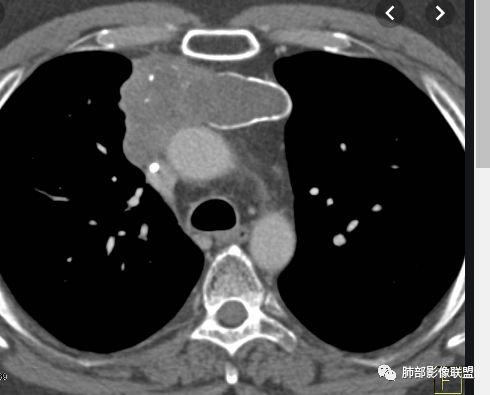

水晶石头:患者老年男性,发现皮肤粘膜黄染5天,右肺占位1天。

胸部CT:右肺中叶内侧段紧邻心脏实性结节,边缘光滑,边界清楚,宽基底与胸膜相连,内可见不规则钙化,钙化内见点状低密度影,增强中度强化,综合考虑良性病变。畸胎瘤可能大,鉴别胸膜孤立性纤维瘤及胸腺瘤。

王秀仙:右侧前纵隔肿块,边缘分叶,周围肺组织推移,宽基底与纵隔胸膜相连,可见胸膜尾征,密度不均,病灶中心可见斑块状钙化,右侧内乳动脉位于病灶前外侧并略增粗,实性成分明显强化,考虑纵隔畸胎瘤,鉴别胸腺瘤。

蓝天白云:定位纵隔,病灶呈实性成分,内见钙化,钙化位于病灶中心,实性成分均匀延迟强化,考虑良性病变,如果胸膜起源考虑sft,纵隔来源胸腺瘤,鉴别畸胎瘤。黄勇老师说过右侧心膈角区可以发生胸腺瘤

右侧前纵膈肿块,边缘分叶,病灶中心可见斑块状钙化,实性成分明显持续强化,考虑胸腺瘤。